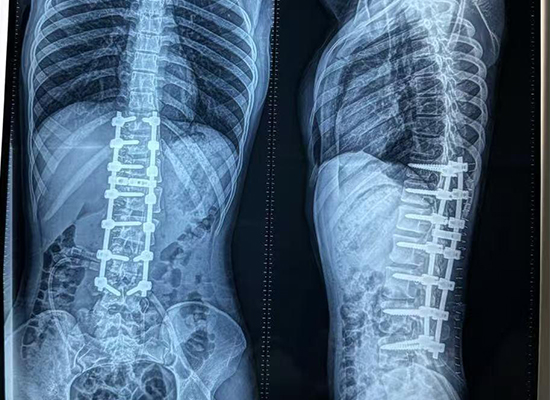

Las imágenes posoperatorias demostraron:

Mejora significativa en la alineación de la columna.

Curvatura reducida y prominencia costal.

Hombros y tronco equilibrados